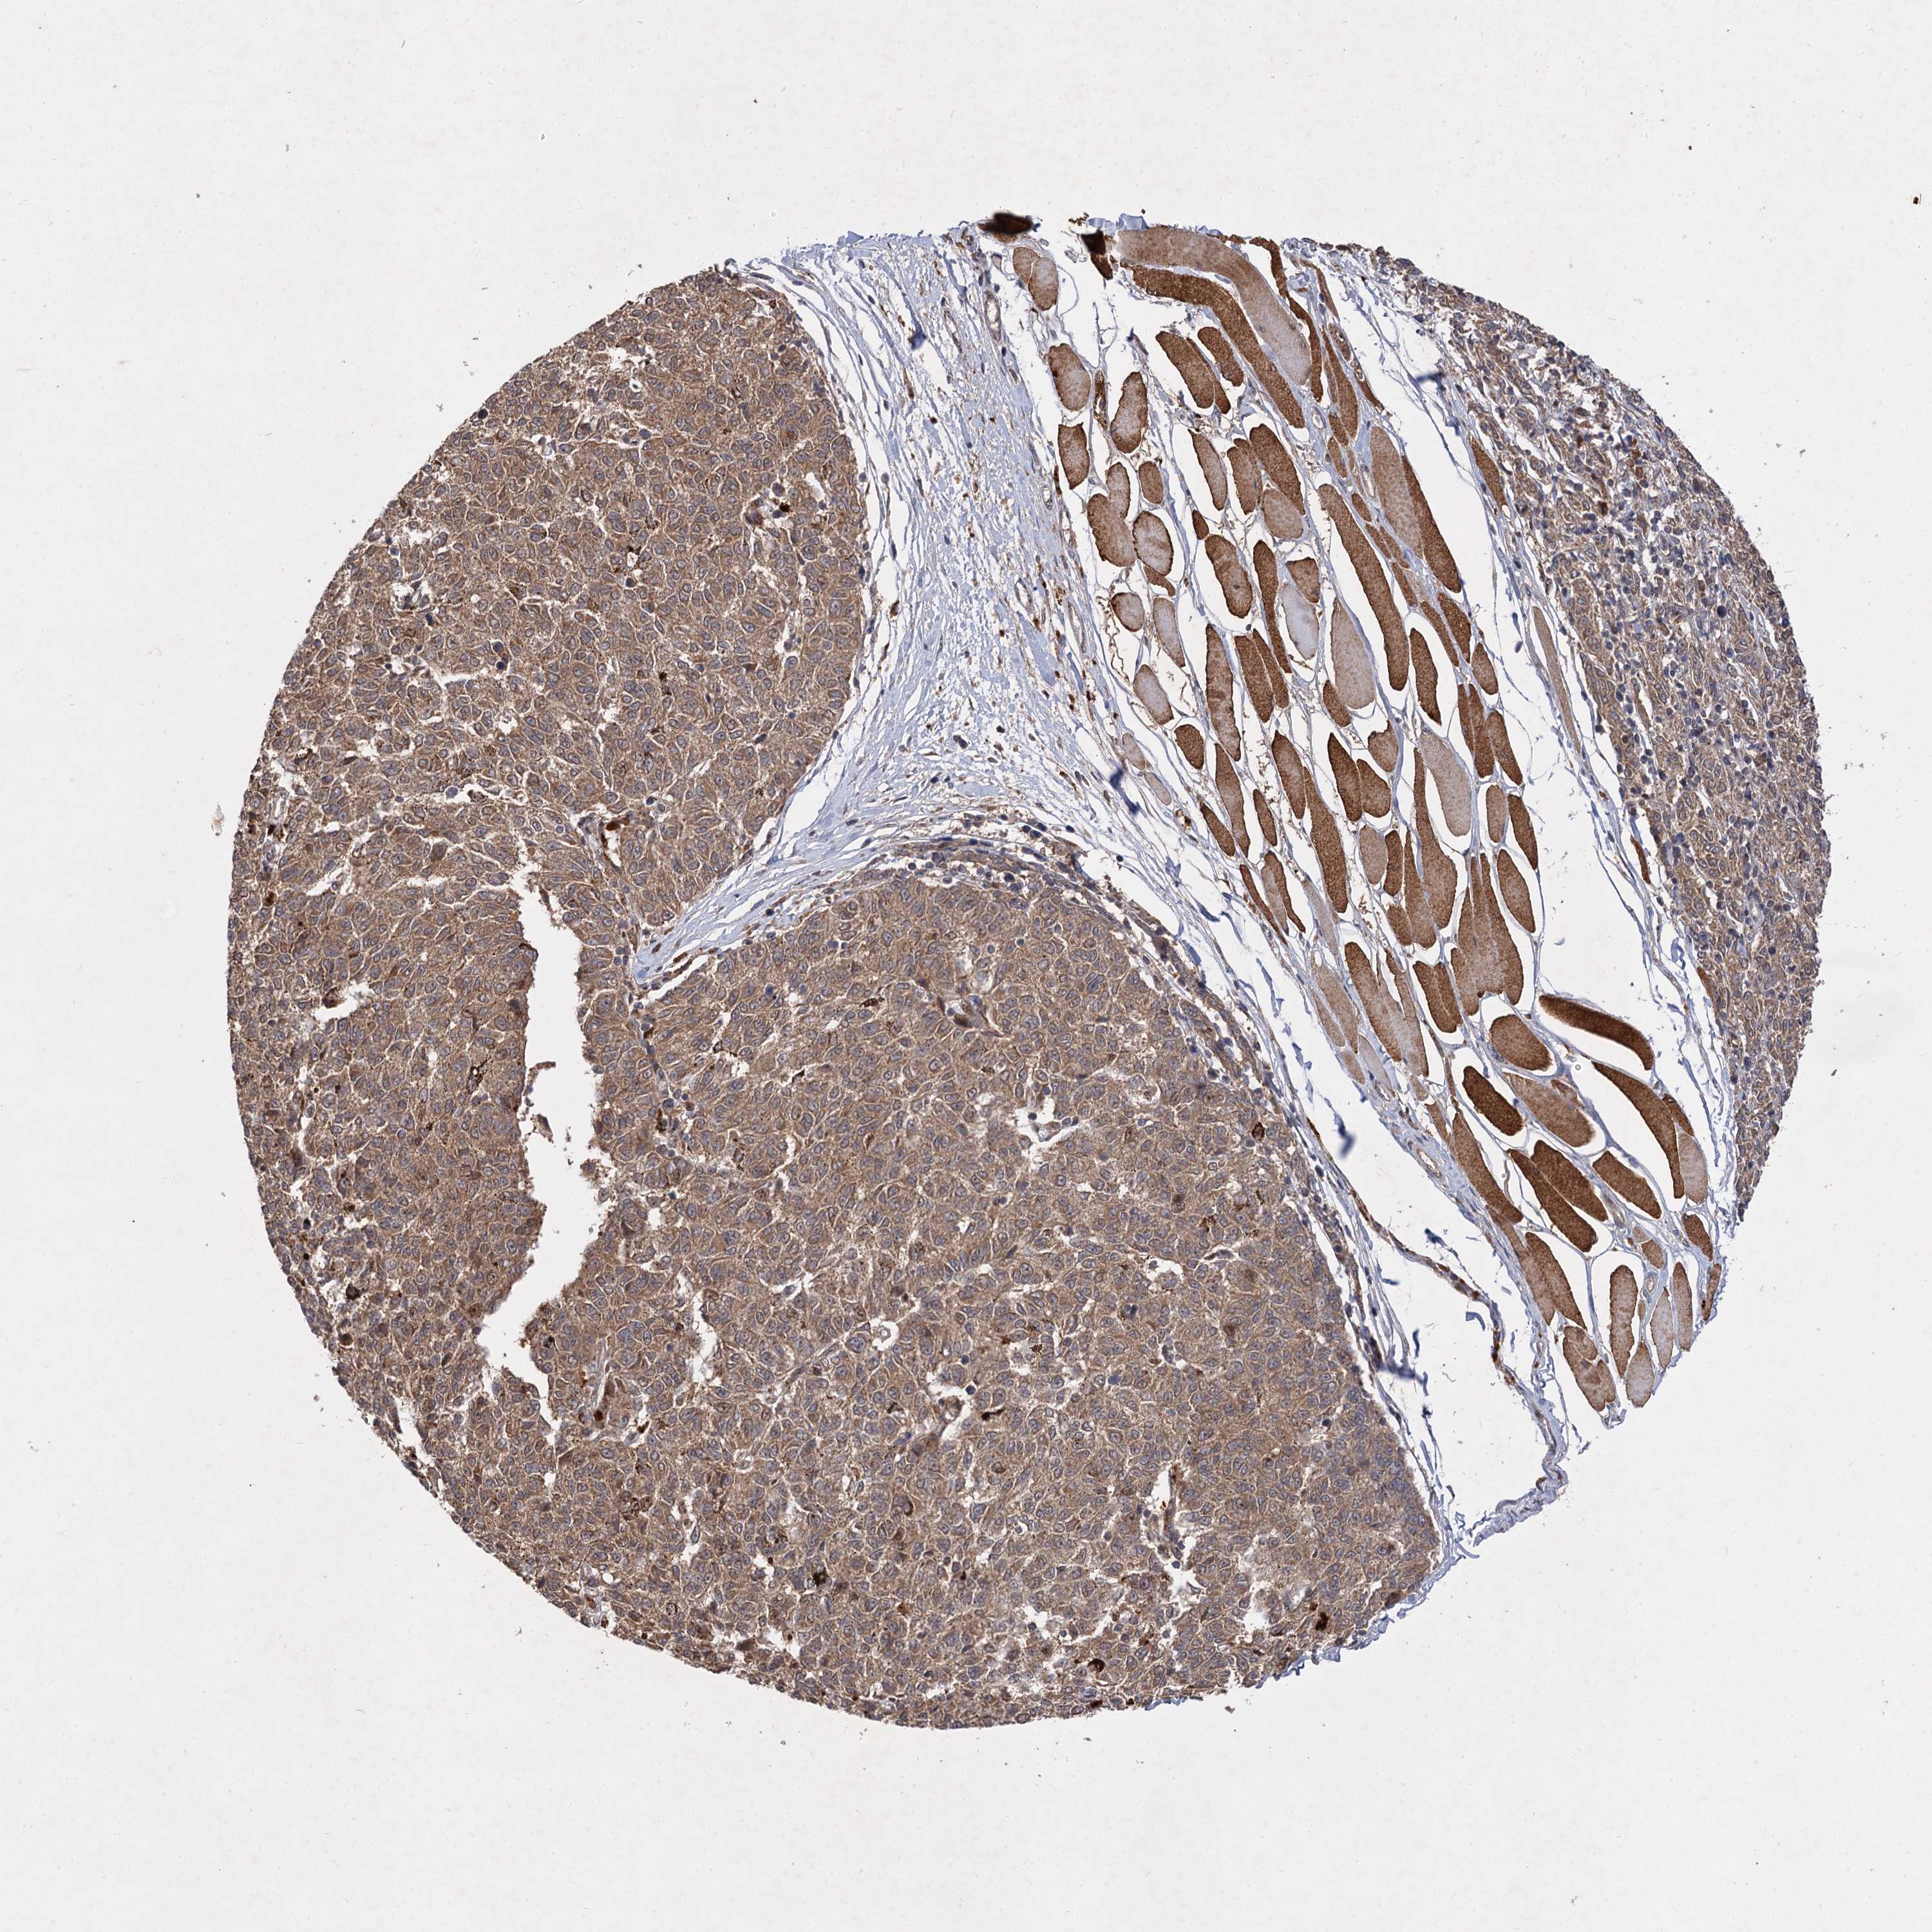

MELANOMA - Protein expressioni

A mouse-over function shows sample information and annotation data. Click on an image to view it in a full screen mode. Samples can be filtered based on level of antibody staining by selecting one or several of the following categories: high, medium, low and not detected. The assay and annotation is described here.

Note that samples used for immunohistochemistry by the Human Protein Atlas do not correspond to samples in the TCGA dataset.

Antibody stainingi

Antibody staining in the annotated cell types in the current human tissue is reported as not detected, low, medium, or high, based on conventional immunohistochemistry profiling in selected tissues. This score is based on the combination of the staining intensity and fraction of stained cells.

Each image is clickable and will lead to virtual microscopy that enables deeper exploration of all samples and also displays staining intensity scores, fraction scores and subcellular localization as well as patient and tissue information for each sample.

Antibody HPA038850

Antibody HPA038851

Malignant melanoma, NOS

Malignant melanoma, Metastatic site